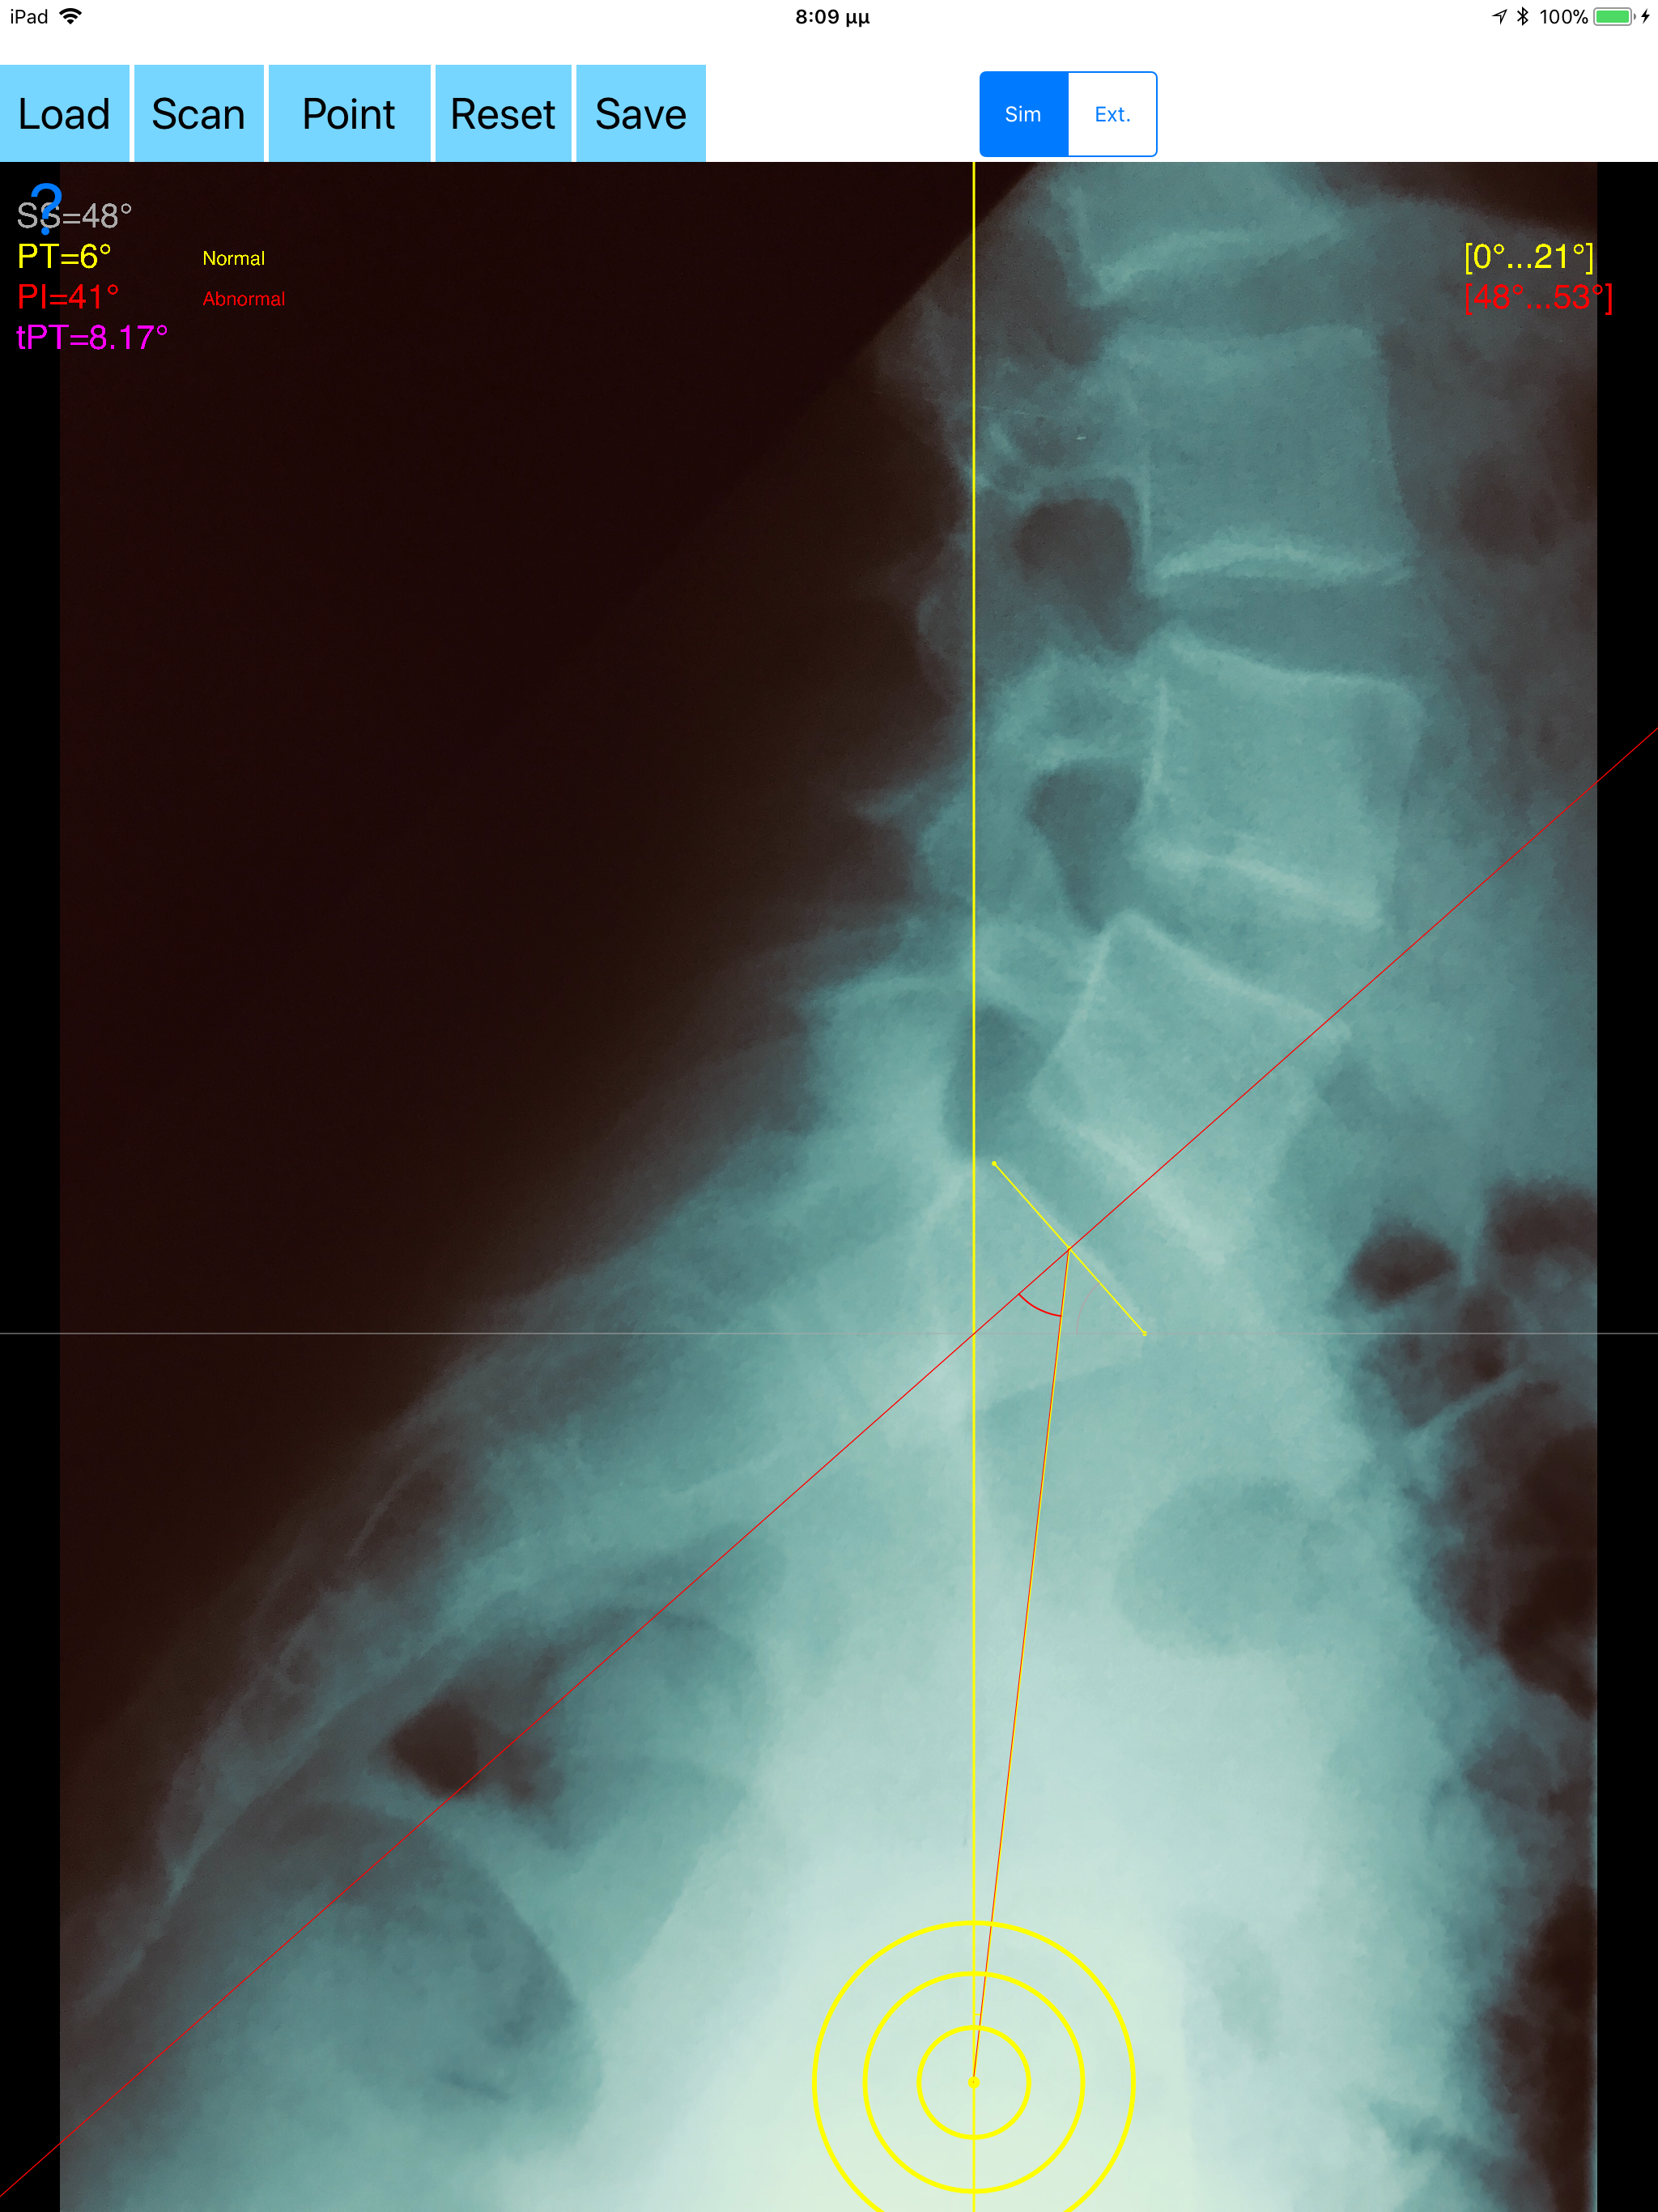

The assessment of the parameters involved in spinopelvic jucture are of paramount importance for spine and joint replacement surgeon. The dynamic interplay between flexibility and balance around the axis of gravity determine the type and the amount of influence in spine and hips. Radiographic parameters to evaluate objectively the spinopelvic sagittal balance are Pelvic incidence (PI), Sacral slope (SS), Pelvic Tilt (PT), Lumbar lordosis (LL). Drawings in patients X-rays and precise measurements are important in order to quantify the magnitude of spinal deformities, to monitor the success or failure of treatment and thus optimise the management of patients according to the severity of the imbalance or even to identify patient at risk of degenerative spondylolisthesis or disk herniation. The Spinopelvic Balance App is medical software aimed for orthopaedic surgeons, providing tools that allow doctors to: -Securely import medical images directly from the camera or stored photos. -By marking few points at the image of X-ray, the App calculates and offers a very convenient way to determine the most accurate possibly way at once, Pelvic incidence (PI), Sacral slope (SS), Pelvic Tilt (PT), Lumbar lordosis (LL), thoracic kyphosis, PI–LL Pelvic incidence Angle (PI) minus Lumbar lordosis Angle (LL) PI–LL, theoretical normal pelvic tilt (tPT),theoretical normal L1-S1 lumbar lordosis (tL1S1), Pelvic Radius Angle (PRA). According to measured parameters the app categorises the severity of the imbalance of spine, in different stages: optimal or non optimal. -Save the planned images, for later review or consultation.The measured values are compared by normal reference databases and also data are exported as txt file, ready to print or to input as cells to excel for research. -The app allows choosing between simple and extended method according to everyday preference and also by choosing points in vertebra body in a independent manner from order. -The app can be used to measure L5 Incidence (L5I) Angle or L4 respectively. -The app offers theoretical value estimation this is particularly useful because a sensible difference between theoretical value and measured value reveals a compensation phenomenon if the pelvis tilt (PT) is higher than its theoretical value, then it is due to pelvis retroversion, which is a compensation phenomenon. Knowing the theoretical value of Pelvis Tilt (PT) provided it is easy to understand that a sensible difference between theoretical value and measured value is a compensation phenomenon. All information received from the software output must be clinically reviewed regarding its plausibility before patient treatment! Spinopelvic Balance App indicated for assisting healthcare professionals. Clinical judgment and experience are required to properly use the software.The software is not for primary image interpretation. In a busy everyday practice, the examiner have to draw lines in X-rays or in clinical settings, this it is time consuming and cumbersome. Accessory instruments like protractors, hinged goniometers, well sharped pencils, rulers or even transparent papers must be available. The app offers a very convenient and accurate way to perform most common radiographic measurements for spine, at the spinopelvic juncture in a blink of an eye in front of your screen. The build in feature of the app, allows results to be categorized may help decide what could be considered normal or pathologic. The app is not a simple goniometer, is an enhanced product which helps to monitor objectively the course of the treatment and evaluate optimally the spine. This App is particular useful in clinical settings where you need a quick results without losing time.Please see tutorial videos at the developer’s web Reference 1.Nunes VR, et al.Spinopelvic balance evaluation of patients with degenerative spondylolisthesis L4L5 and L4L5 herniated disc who underwent surgery.Rev Bras Ortop. 2016 Sep 22;51(6):662-666.